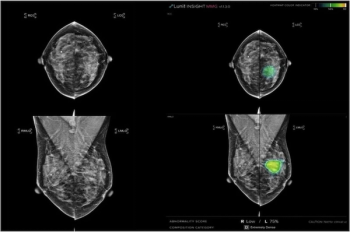

In a study involving over 24,000 women, two-thirds of whom had dense breasts, adjunctive AI led to a significantly higher rate of cancer detection for breast radiologists with no difference in recall rates.